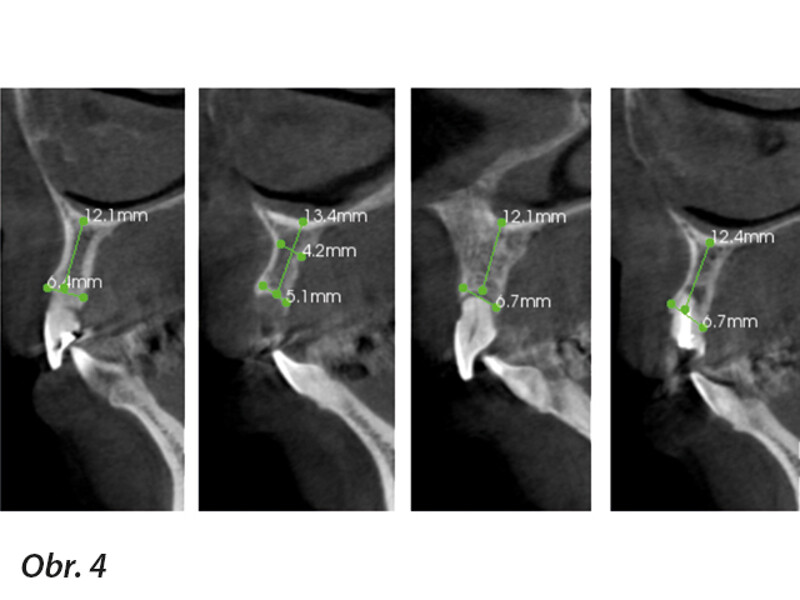

Okamžitá implantace a CADCAM